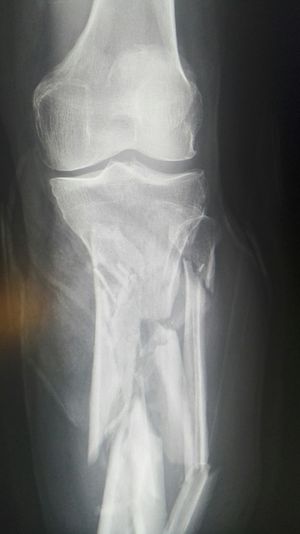

Xray

Accident

Fractures

Tibia

Fibula

Shattered!!!!!!!